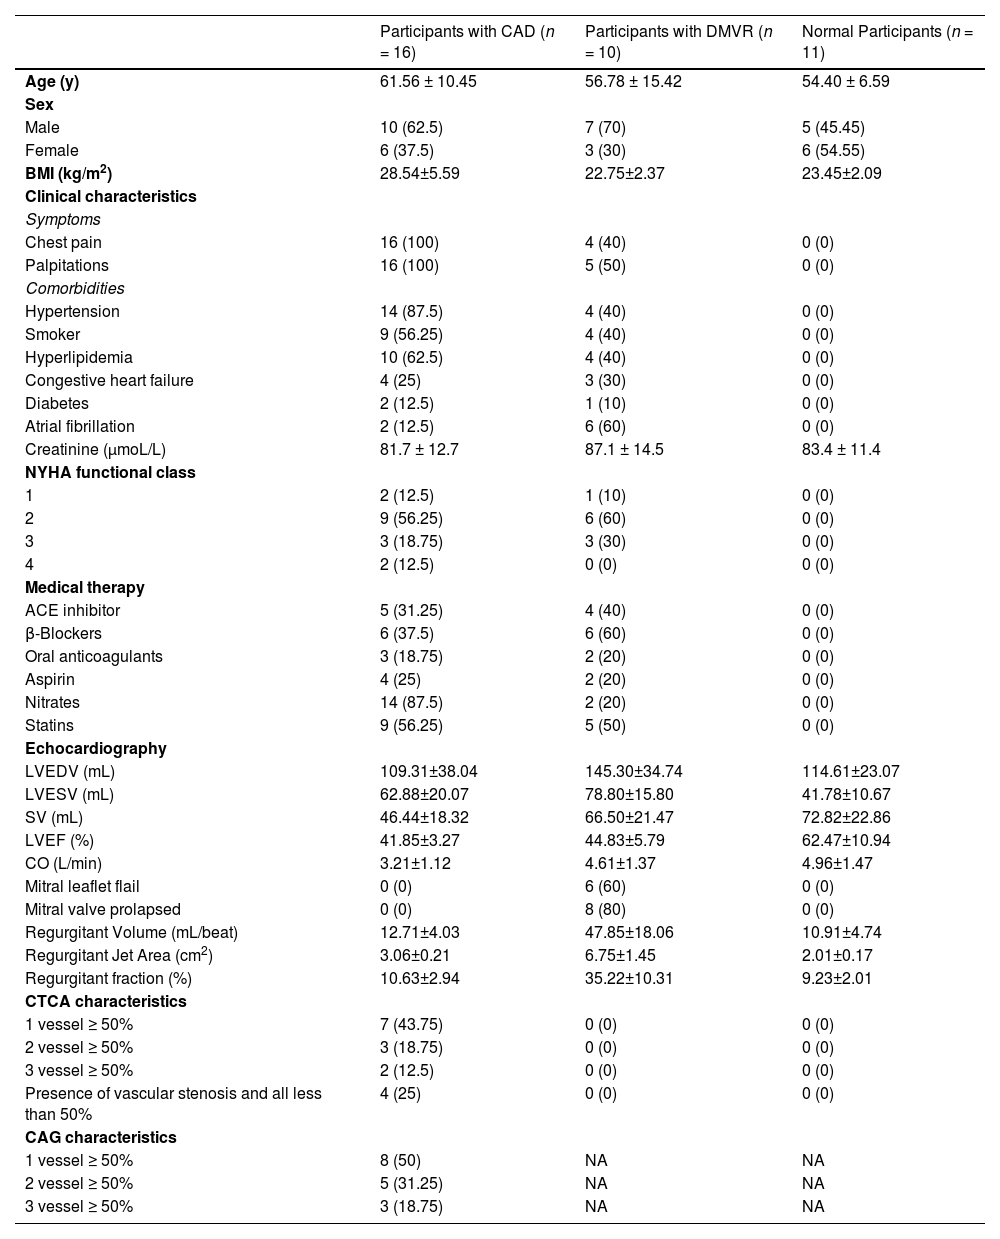

ResultsStudy cohortAmong the 256 patients with heart diseases, 89 who had undergone invasive interventions were excluded (percutaneous coronary intervention [n = 46], coronary artery bypass grafting [n = 12], and radiofrequency ablation [n = 31]). The remaining 167 patients, without a history of invasive intervention for heart disease, were screened using echocardiography. Based on the echocardiogram results, 52 patients with the following conditions were excluded (congenital heart disease [n = 8], cardiomyopathy [n = 23], pericardial effusion [n = 35], and combination of valvular and ischemic heart disease [n = 41]). The remaining participants were divided into two groups: patients with valvular disease and LVMD (n = 39) and patients with ischemic heart disease and LVMD (n = 21). Furthermore, after excluding 26 patients with two or more valvular diseases in the valvular disease group, the remaining 13 patients were included in the isolated DMVR group. Of the 21 patients in the ischemic heart disease group, 18 were included in the pure CAD group after exclusion of three patients who were intolerant to CTA examination. Moreover, three and two patients from the isolated DMVR and pure CAD groups, respectively, were excluded owing to intolerance to CMR examination. Finally, 10 patients with DMVR were included in the group of isolated DMVR (mean age, 57 ± 15 years). The CAD group included 16 patients (mean age, 62 ± 10 years). Additionally, 11 age- and sex-matched healthy volunteers (mean age, 54 ± 7 years) were included as controls. The detailed characteristics of the participants are summarized in Table 1 and Fig. 1.

Demographics characteristics of study participants at evaluation.

| Participants with CAD (n = 16) | Participants with DMVR (n = 10) | Normal Participants (n = 11) | |

|---|---|---|---|

| Age (y) | 61.56 ± 10.45 | 56.78 ± 15.42 | 54.40 ± 6.59 |

| Sex | |||

| Male | 10 (62.5) | 7 (70) | 5 (45.45) |

| Female | 6 (37.5) | 3 (30) | 6 (54.55) |

| BMI (kg/m2) | 28.54±5.59 | 22.75±2.37 | 23.45±2.09 |

| Clinical characteristics | |||

| Symptoms | |||

| Chest pain | 16 (100) | 4 (40) | 0 (0) |

| Palpitations | 16 (100) | 5 (50) | 0 (0) |

| Comorbidities | |||

| Hypertension | 14 (87.5) | 4 (40) | 0 (0) |

| Smoker | 9 (56.25) | 4 (40) | 0 (0) |

| Hyperlipidemia | 10 (62.5) | 4 (40) | 0 (0) |

| Congestive heart failure | 4 (25) | 3 (30) | 0 (0) |

| Diabetes | 2 (12.5) | 1 (10) | 0 (0) |

| Atrial fibrillation | 2 (12.5) | 6 (60) | 0 (0) |

| Creatinine (μmoL/L) | 81.7 ± 12.7 | 87.1 ± 14.5 | 83.4 ± 11.4 |

| NYHA functional class | |||

| 1 | 2 (12.5) | 1 (10) | 0 (0) |

| 2 | 9 (56.25) | 6 (60) | 0 (0) |

| 3 | 3 (18.75) | 3 (30) | 0 (0) |

| 4 | 2 (12.5) | 0 (0) | 0 (0) |

| Medical therapy | |||

| ACE inhibitor | 5 (31.25) | 4 (40) | 0 (0) |

| β-Blockers | 6 (37.5) | 6 (60) | 0 (0) |

| Oral anticoagulants | 3 (18.75) | 2 (20) | 0 (0) |

| Aspirin | 4 (25) | 2 (20) | 0 (0) |

| Nitrates | 14 (87.5) | 2 (20) | 0 (0) |

| Statins | 9 (56.25) | 5 (50) | 0 (0) |

| Echocardiography | |||

| LVEDV (mL) | 109.31±38.04 | 145.30±34.74 | 114.61±23.07 |

| LVESV (mL) | 62.88±20.07 | 78.80±15.80 | 41.78±10.67 |

| SV (mL) | 46.44±18.32 | 66.50±21.47 | 72.82±22.86 |

| LVEF (%) | 41.85±3.27 | 44.83±5.79 | 62.47±10.94 |

| CO (L/min) | 3.21±1.12 | 4.61±1.37 | 4.96±1.47 |

| Mitral leaflet flail | 0 (0) | 6 (60) | 0 (0) |

| Mitral valve prolapsed | 0 (0) | 8 (80) | 0 (0) |

| Regurgitant Volume (mL/beat) | 12.71±4.03 | 47.85±18.06 | 10.91±4.74 |

| Regurgitant Jet Area (cm2) | 3.06±0.21 | 6.75±1.45 | 2.01±0.17 |

| Regurgitant fraction (%) | 10.63±2.94 | 35.22±10.31 | 9.23±2.01 |

| CTCA characteristics | |||

| 1 vessel ≥ 50% | 7 (43.75) | 0 (0) | 0 (0) |

| 2 vessel ≥ 50% | 3 (18.75) | 0 (0) | 0 (0) |

| 3 vessel ≥ 50% | 2 (12.5) | 0 (0) | 0 (0) |

| Presence of vascular stenosis and all less than 50% | 4 (25) | 0 (0) | 0 (0) |

| CAG characteristics | |||

| 1 vessel ≥ 50% | 8 (50) | NA | NA |

| 2 vessel ≥ 50% | 5 (31.25) | NA | NA |

| 3 vessel ≥ 50% | 3 (18.75) | NA | NA |

Values are n (%) or mean ± SD.

ACE, Angiotensin-Converting Enzyme; CAD, Coronary Artery Disease; CAG, Coronary Arteriography; CTCA, Computed Tomography Coronary Angiography; LVEDV, Left Ventricular End-Diastolic Volume; LVESV, Left Ventricular End-Systolic Volume; DMVR, Degenerative Mitral Valve Regurgitation; NA, No Data; NYHA, New York Heart Association; SV, Stroke Volume; LVEF, Left Ventricular Ejection Fraction; CO, Cardiac Output.